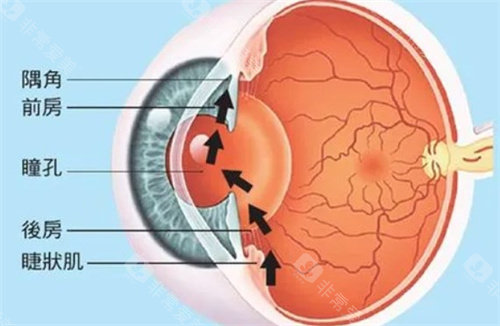

小梁切除术:针对开角型青光眼,通过改良缝合技术减少术后低眼压风险,单眼手术时长缩短至25分钟。

青光眼引流阀植入术:采用3D导航系统定位,植入比较准度提升,尤其适合难治性青光眼患者。

复合式小梁切除:结合抗代谢药物应用,手术可行性提升,尤其适合年轻患者。

激光虹膜边缘成形术:针对急性青光眼发作,10分钟内快速降低眼压,避免视力进一步损伤。

青光眼白内障联合手术:一次手术解决两种眼病,减少患者反复麻醉风险,术后视力修复周期缩短。

小创口青光眼手术(MIGS):通过微小切口植入iStent引流管,创伤小,适合早期青光眼患者。

前房穿刺术:针对急性青光眼眼压飙升,30秒内完成房水释放,快速缓解眼痛症状。

选择性激光小梁成形术(SLT):没有创口治疗早期青光眼,可重复操作,避免药物副作用。

个性化小梁切除术:根据角膜生物力学数据调整手术参数,术后散光发生率降低。

青光眼引流阀动态调节术:通过智能阀门控制房水流出量,避免术后眼压波动。